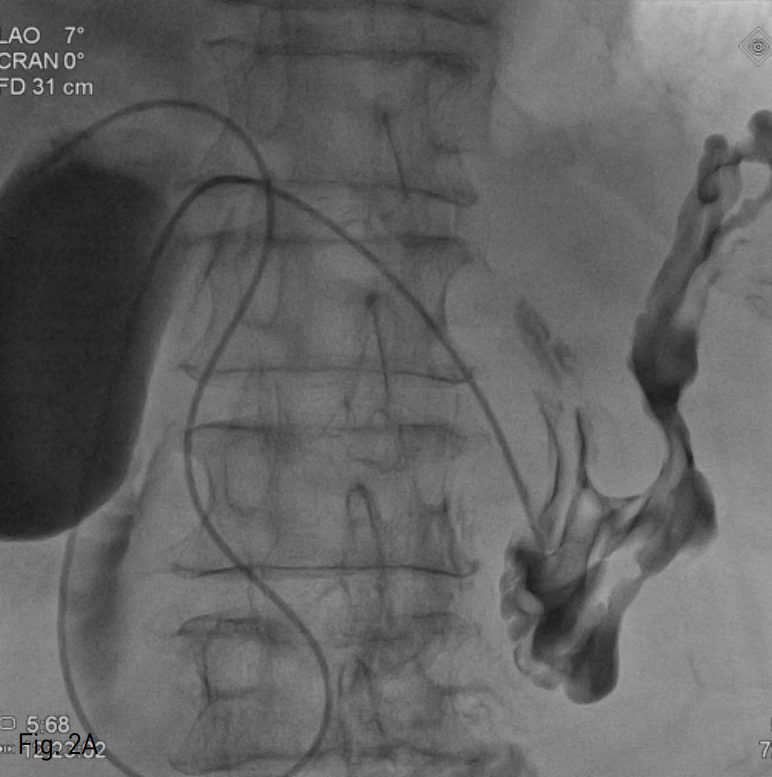

Fig. 2

A. Fluoroscopic image shows retrograde passage of air insufflation catheter through percutaneous transhepatic gallbladder drainage to the stomach.

먼저 위 공기 팽창을 위해 Gastro-tube를 삽입하려고 시도하였으나 하인두 이하로 진입이 불가능 하였다. 초기 투시경 사진상 장시간의 금식으로 인해 위장은 허탈되어 있고, 횡행 결장의 공기 음영이 상복부에 위치하여, 위 공기 팽창이 필수적이라고 생각되었다. 먼저 술자의 이전 경험에 비추어 22G Chiba needle과 hairwire (A&A medical, Seoul, Korea)를 이용하여 우측 간내 담관을 천자하여 위내 공기 팽창용 catheter를 삽입하려 하였으나, 환자의 척추 후만증으로 인한 자세불안정과 늘어나지 않은 상태의 정상 우측 담관 구조로 인해 천자에 실패하였다. 그래서 초음파 유도하에 담낭을 천자하여, 5 Fr angio-sheath (Terumo, Tokyo, Japan)를 설치하였다. Sheath를 통하여, 다시 0.035 inch guide wire (Terumo, Tokyo, Japan)와 5Fr Cobra catheter (Cook, Bloomington, IN,USA)를 이용하여 후향적으로 위 분문부에 진입하였다 (Fig.2A). 실내 공기 500cc를 주입하여 위를 팽창시킨 후 약간의 조영제를 주입하여 위벽 주름을 조영하였다. 다시 복벽을 리도카인을 이용하여 국소 마취한 후, 복직근 외연부 라인에서 적당한 위 분문부를 위저방향으로 22G Chiba needle과 hair wire (A&A medical, Seoul, Korea)를 이용하여 위 주름이 밀리는 것을 관찰하며 천자하였다. 다시 4 Fr sheath (Cook, Bloomington, IN, USA)를 거치한 후 T자형 고정 장치를 삽입하였고, 통상적인 위창냄술의 방법대로 경로를 확장하였다. 12 Fr 위창냄술 튜브 (Cook, Bloomington, IN, USA)를 삽입하고, 조영제를 주입하여 튜브의 위치와 기능, 복강 내로 유출이 있는지를 확인하였다 (Fig. 2B). 마지막으로 T자형 고정장치와 튜브를 피부에 고정하였고, 이후 담낭 내에 8.5 Fr Pigtail catheter (Cook, Bloomington,IN,USA)를 거치 한 후 시술을 종료 하였다.